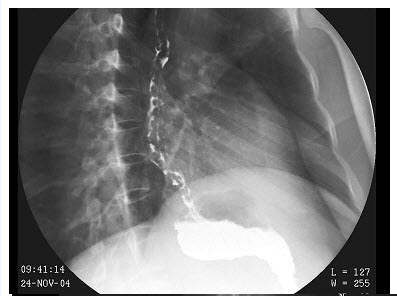

患者,男,40岁,因进食困难,逐渐加重半年就诊,钡餐造影检查示食管明显扩张,蠕动减弱,食管远端呈鸟嘴状,表面尚光整,服温水后,对比剂部分进入胃内。钡餐检查如图所示

最可能诊断为()

A.食管下端癌

B.食管贲门失弛缓症

C.食管下端静脉曲张

D.反流性食管炎

E.食管下段黏膜下平滑肌瘤

点击查看答案